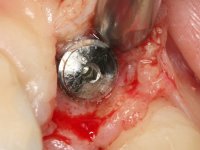

In the initial phase, it was proposed to the patient to perform the surgical implant exposure and after clinical evaluation, make prosthetic decisions. Once the healing screw was placed and the soft tissues were healed, an inadequate position of the implant was found. In view of the dramatic situation, the patient was proposed to remove the implant and put a new one after tissue regeneration. This proposal was rejected by the patient, who suggested temporary rehabilitation of the current implant. A new proposal was then made, to rehabilitate the implant, consisting of a screwed abutment, and on this, the placement of an acrylic crown with coronal and gingival components. After 6 years with the provisional treatment, the patient appeared in consultation with an abscess in tooth 1.1. After clinical and imaging analysis, it was decided to remove teeth 1.1 and 2.2, submerge the implant, place two implants at the site of 1.1 and 2.2 and perform adequate tissue regeneration. Temporization would be done with a provisional 3-element bridge, adhered with a net to the neighboring teeth. After osseointegration, definitive rehabilitation would be done with a 3-element bridge, including zirconia infrastructure and ceramic cover.

The surgical implant exposure and the healing screw placement proved to be a negative surprise regarding its position. Since the proposed removal of the implant was refused, we advanced to its provisional rehabilitation. An open tray impression technique was done, and a screwed abutment with a coronal and gingival component and an acrylic crown were made in the laboratory, using these two components. The provisional crown was placed in the mouth until a final decision was made. Six years passed before the patient returned to the clinic with an abscess on tooth 1.1. The choice to remove teeth 1.1 and 2.2 was made, to create a provisional 3-element bridge with a net to be adhered to the adjacent teeth. Surgery was planned and performed, placing the two implants at the site of 1.1 and 2.2, and the implant at the 2.1 site was cut with the objective of submerging it, while adequate tissue regeneration was performed (Surgical Work performed By Dr. Manuel Neves). During osseointegration, the patient used the fixed provisional bridge. A first impression was made for confection of a zirconia screwed provisional bridge, which worked the soft tissues for twelve weeks. The definitive impression was made with the individualisation of custom impression copings. Final rehabilitation was done with ceramized abutments, and also a bridge with zirconia infrastructure and ceramic cover. Due to the inclination of the implant placed at the site of tooth 1.1, the bridge required cemented fixation.